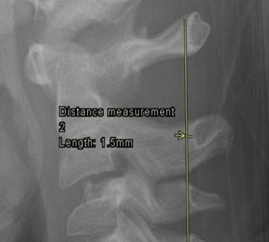

2. Pseudosubluxation of C2

Physiological anterior displacement of C2 on C3 is commonly seen in children, usually <7 years of age, less commonly in older children. It is most commonly seen at C2 on C3, but may less often be seen at C3 on C4. This finding is more pronounced in flexion and can present confusion in the presence of traumatic cervical injury .2 Utilization of Swischuk’s line is useful in differentiating pathological anterior cervical spine displacement from physiological displacement. This line is drawn from the anterior aspect of posterior arch of C1 to anterior aspect of posterior arch of C3 3 and should measure less than 2-mm. A measurement of greater than 2-mm indicates true subluxation. It is important to note that this line should only be used in the absence of other signs of instability and in the absence of prevertebral soft tissue swelling.

Figure 3: a) Pseudosubluxation in a 5-year-old. b) Zoomed in view to demonstrate Swischuk’s line. Case courtesy of Radiopaedia.